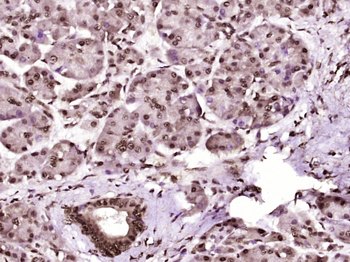

文献和实验:使用 Anti-phospho-Akt (Ser473) Rabbit mAb 对石蜡包埋的人乳腺癌组织进行免疫组织化学分析。(图 A)使用免疫组化试剂盒M&R HRP/DAB Detection IHC Kit,抗体 1:100 稀释;(图 B) 采用普通免疫组化试剂盒,抗体 1:25 稀释。 图 6 免疫组化实验检测 Erk1/2 表达 注:使用 Anti-Erk1/2 Mouse mAb与p44/42 MAPK (Erk1/2)Rabbit mAb 对正常小鼠心脏组织进行免疫